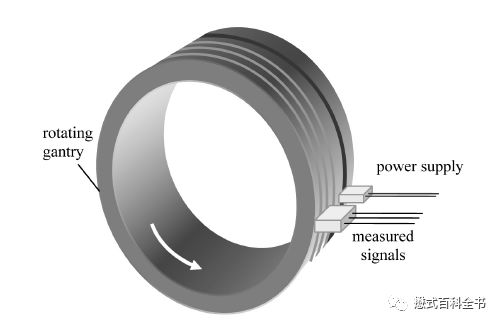

图8:滑环技术原理示意图

第一次飞越是由非螺旋CT发展为螺旋CT,英文Spiral CT或Helical CT,主要的技术革新是利用了滑环技术,探测器可以连续旋转,这次飞越使CT摆脱了逐层扫描的模式。传统的非螺旋CT扫描模式采用的是进步-采集模式,即step-and-shot。这种采集方式包含了两个周期:数据采集周期和非数据采集周期。在数据采集周期,病人不动(扫描床位置不动),X线球管和探测器以一定速度绕病人旋转一周,采集数据;当一层数据采集完成以后,进入非数据采集周期,扫描床移动到下一个扫描位置,等待新的数据采集周期。可以发现,螺旋CT出来之前,CT扫描是采用逐层扫描进床的模式,扫描速度非常慢,而且容易产生伪影,也不方便做一些受呼吸运动影响大的部位。